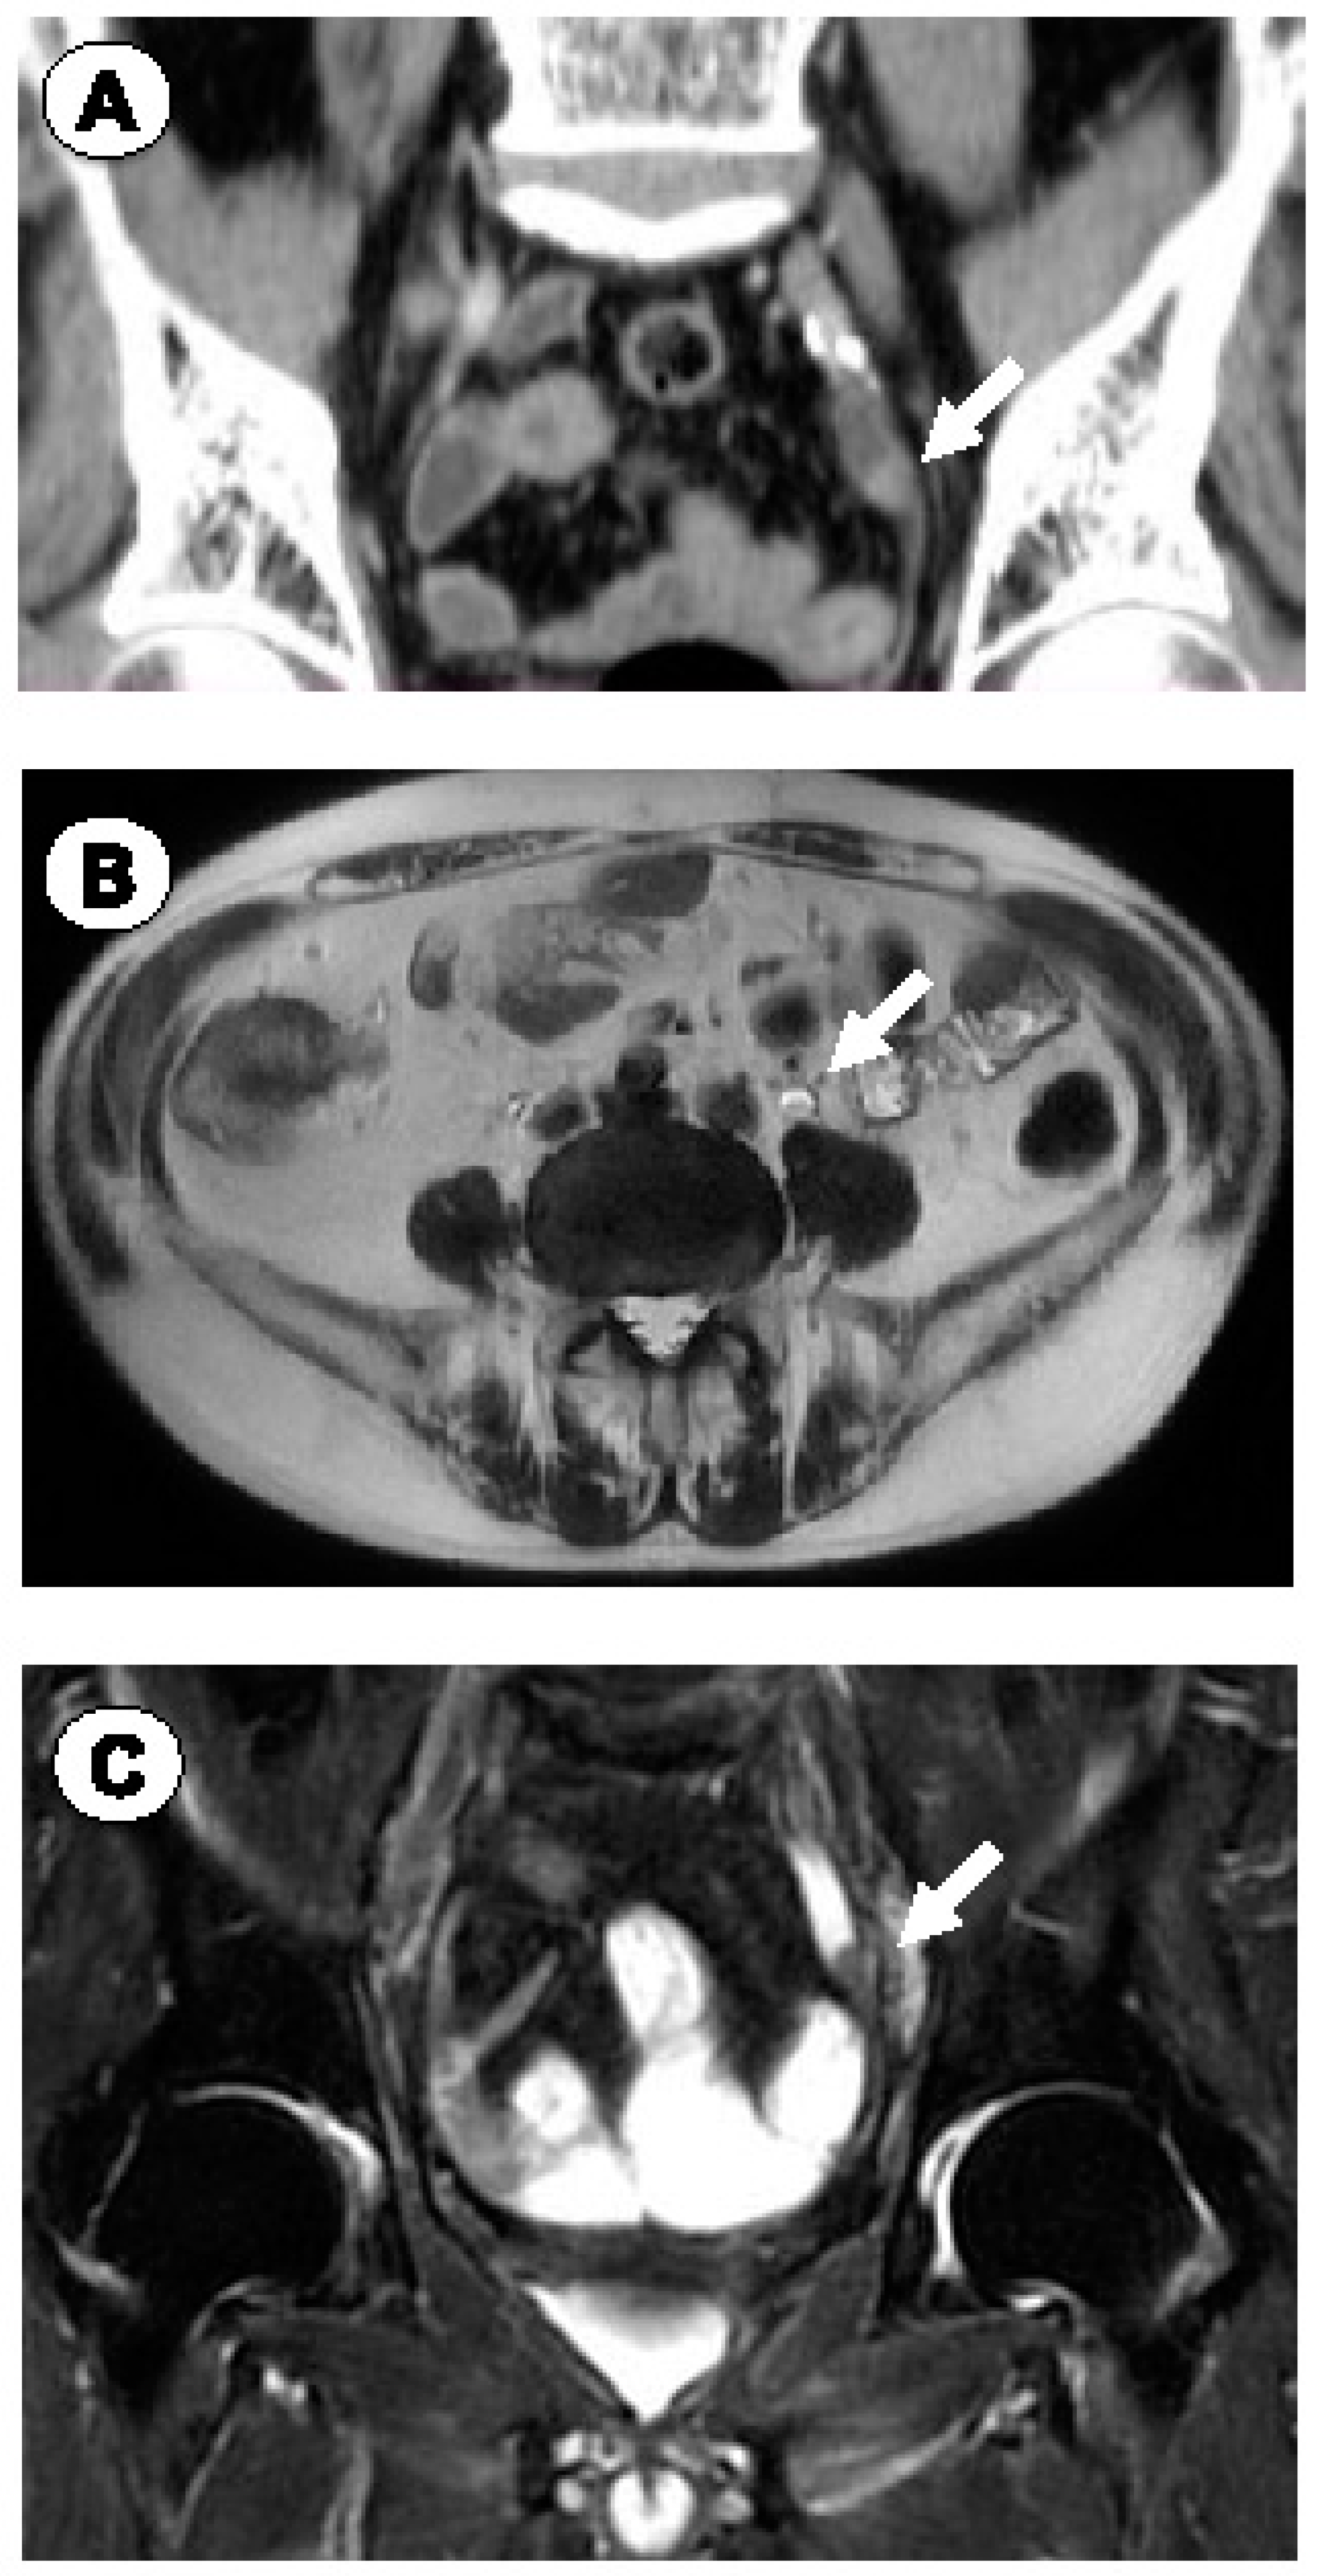

2.1. Case 1

2.2. Case 2

2.3. Case 3